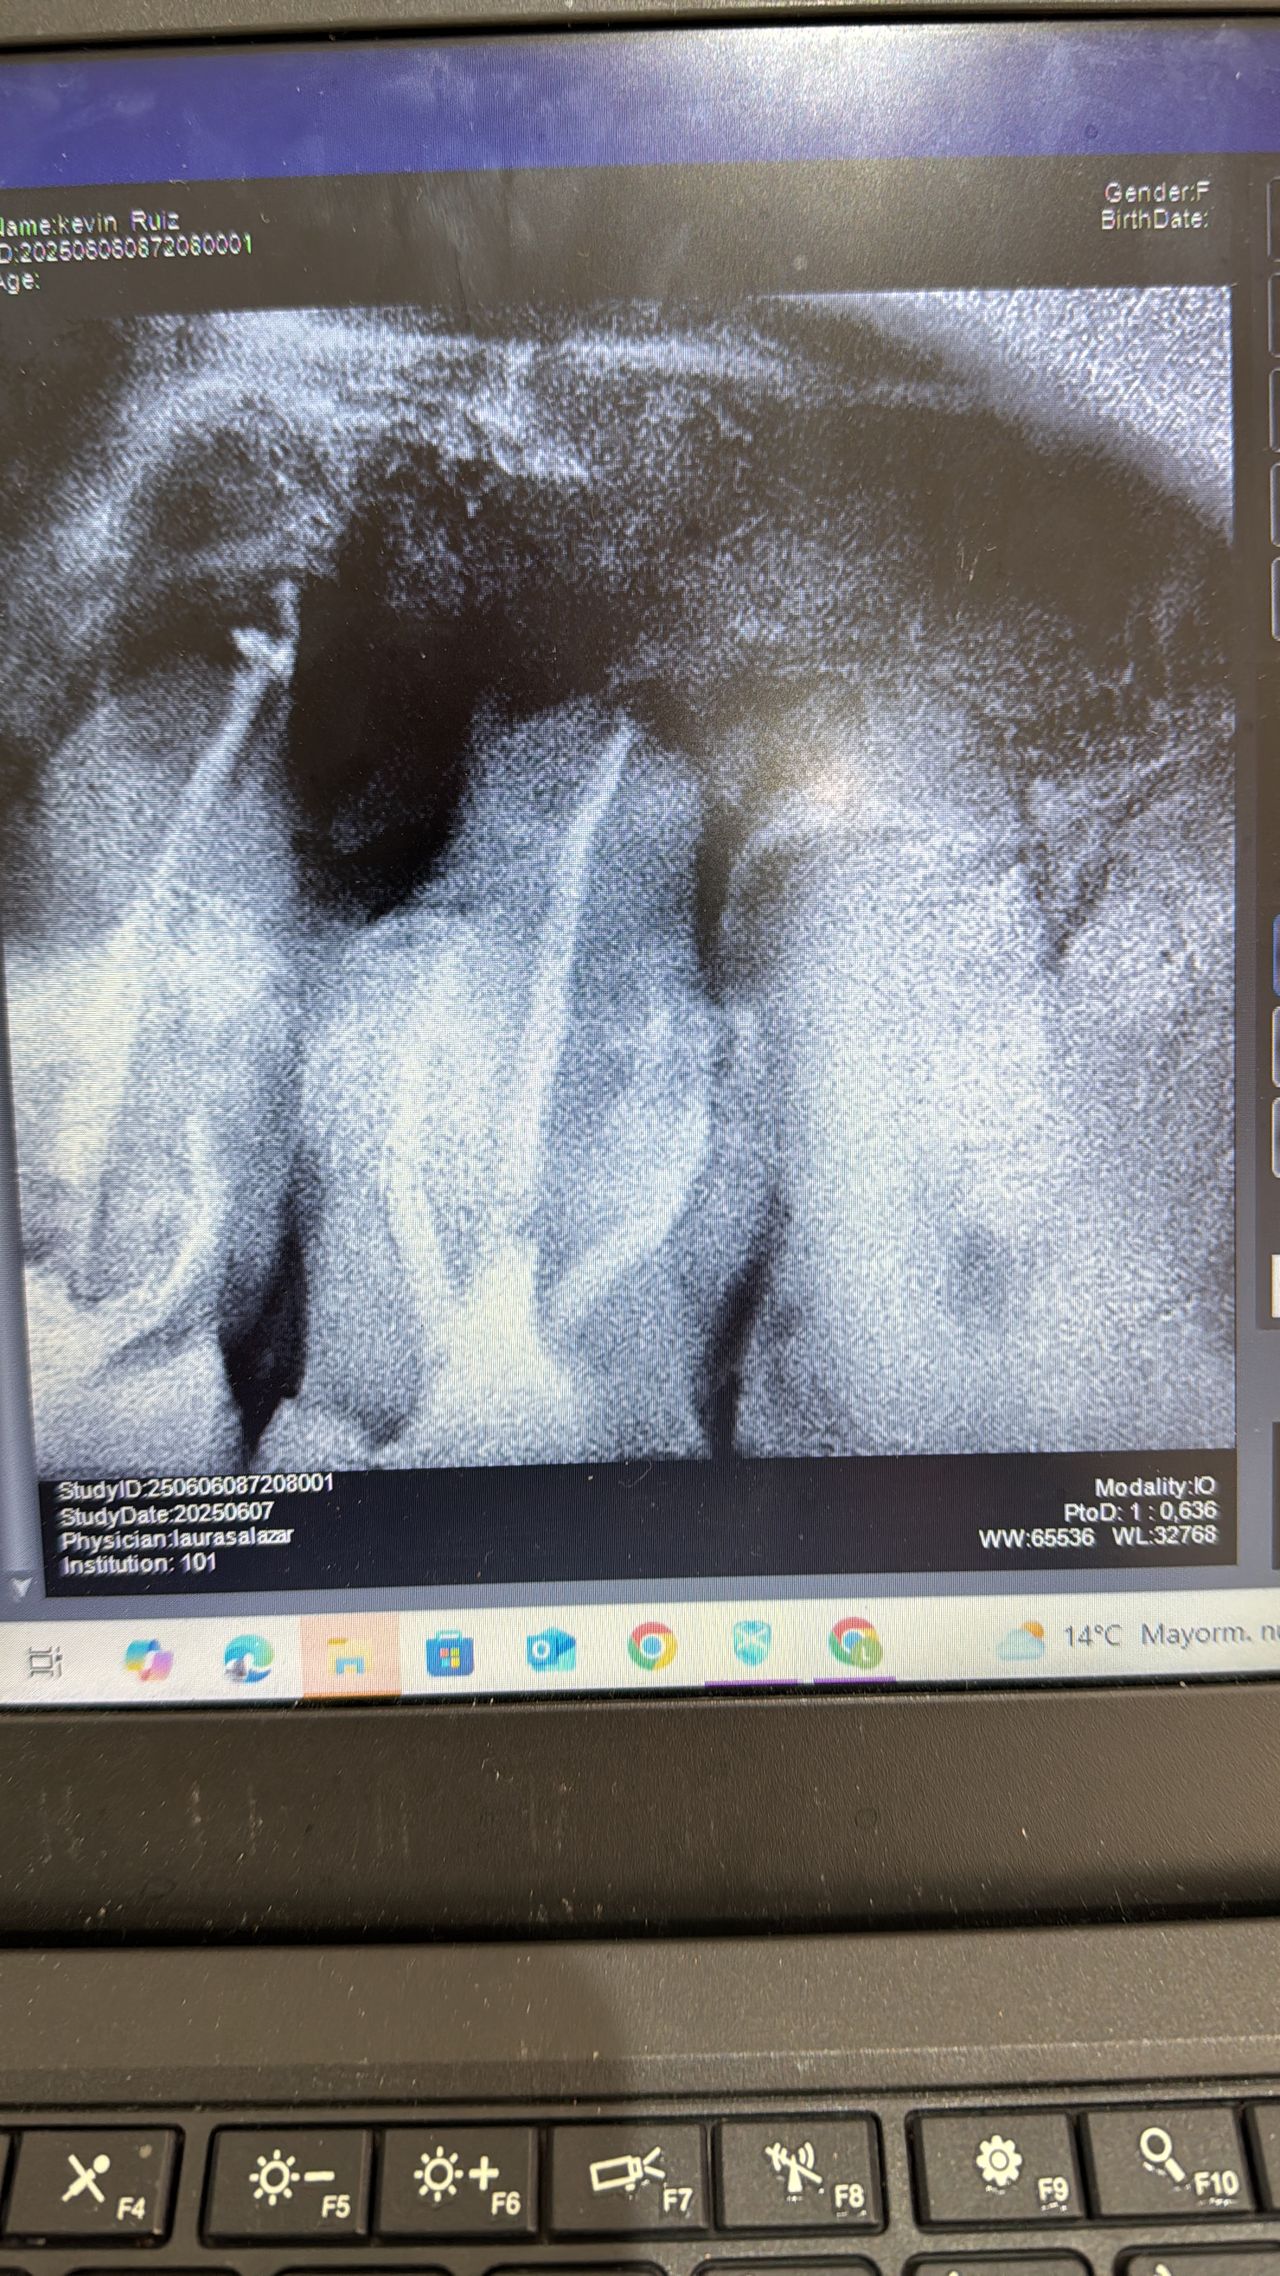

Fotos y videos